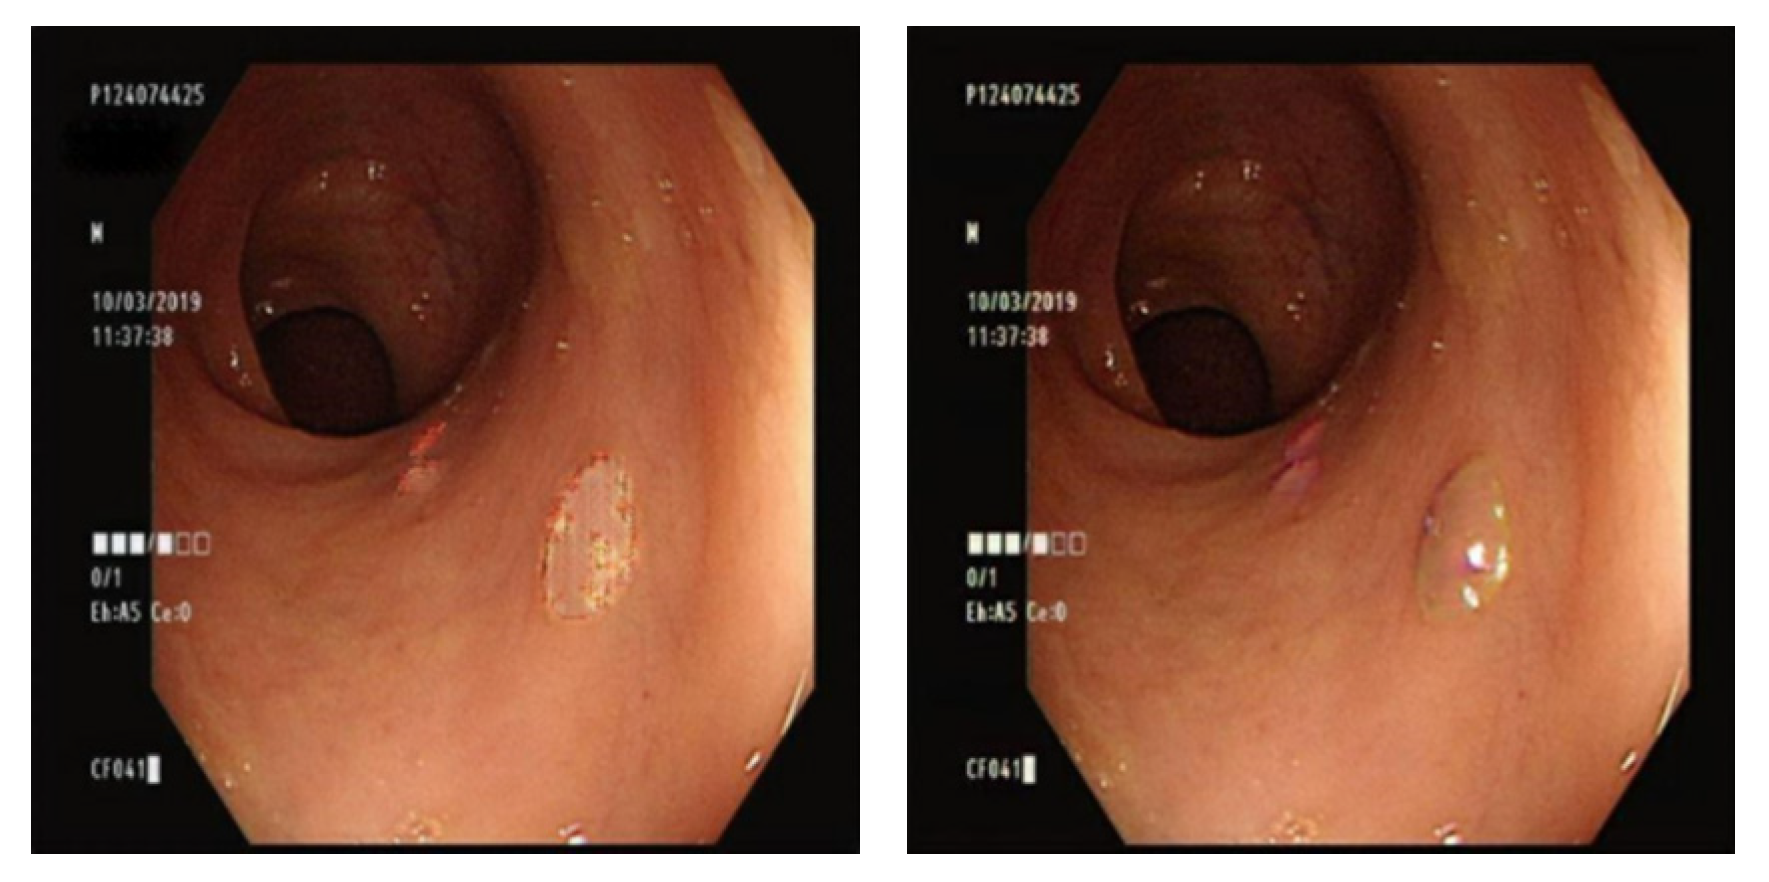

3.8. YOLO Data Labeling